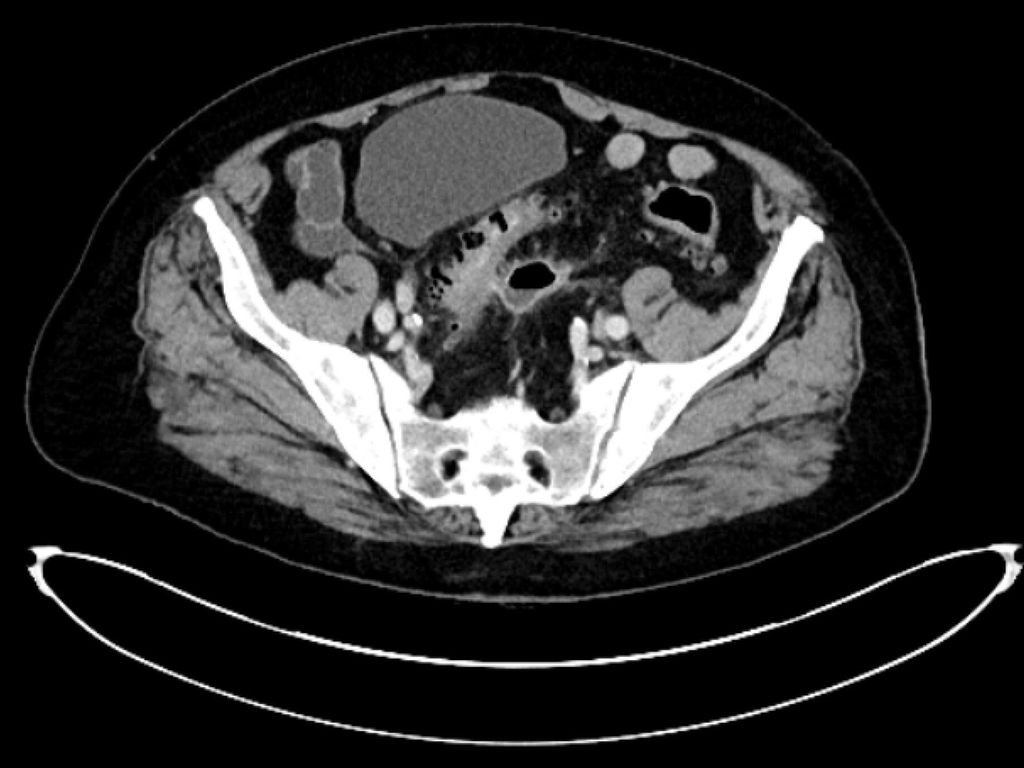

maladie diverticulaire/diverticulite simple aiguë (type 1a–b) (Fig. 1),

diverticulite compliquée aiguë (type 2a–c) (Fig. 2 et 3) et

maladie diverticulaire chronique (maladie diverticulaire symptomatique récidivante ou persistante; type 3a–c) (Fig.4).

Pour la classification de la diverticulite sigmoïdienne, la «Classification of Diverticular Disease» (CDD) s’est imposée (Tab. 1). Celle-ci a pour but de recueillir les différentes évolutions indépendamment d’une opération ainsi que de stratifier les différents pronostics et options thérapeutiques lors du premier diagnostic ou en cas de récidive. Une distinction est faite entre les formes suivantes:

La diverticulite compliquée aiguë de type 2 distingue, avec les types 2a et 2b, la perforation couverte avec micro-abcès (≤3cm) et macro-abcès (>3cm). Le type 2c désigne la perforation libre avec péritonite purulente ou fécale. La diverticulite compliquée aiguë nécessite une hospitalisation et doit être traitée par une antibiothérapie. Si l’apport en liquides est insuffisant, il convient de substituer les liquides par voie parentérale. Un apport alimentaire adapté à la situation peut être mis en place. Contrairement au macro-abcès de type 2b, le micro-abcès de type 2a n’est pas accessible au drainage interventionnel. Si le traitement est efficace, il n’y a pas forcément d’indication d’une opération élective. Il convient de noter que le risque de récidive est corrélé à la taille de l’abcès. Les abcès rétropéritonéaux ou péricoliques (>3cm) peuvent faire l’objet d’un drainage interventionnel. Après une thérapie conservatrice ou interventionnelle réussie de la diverticulite, une opération peut être proposée dans l’intervalle sans inflammation, après environ 6 semaines.